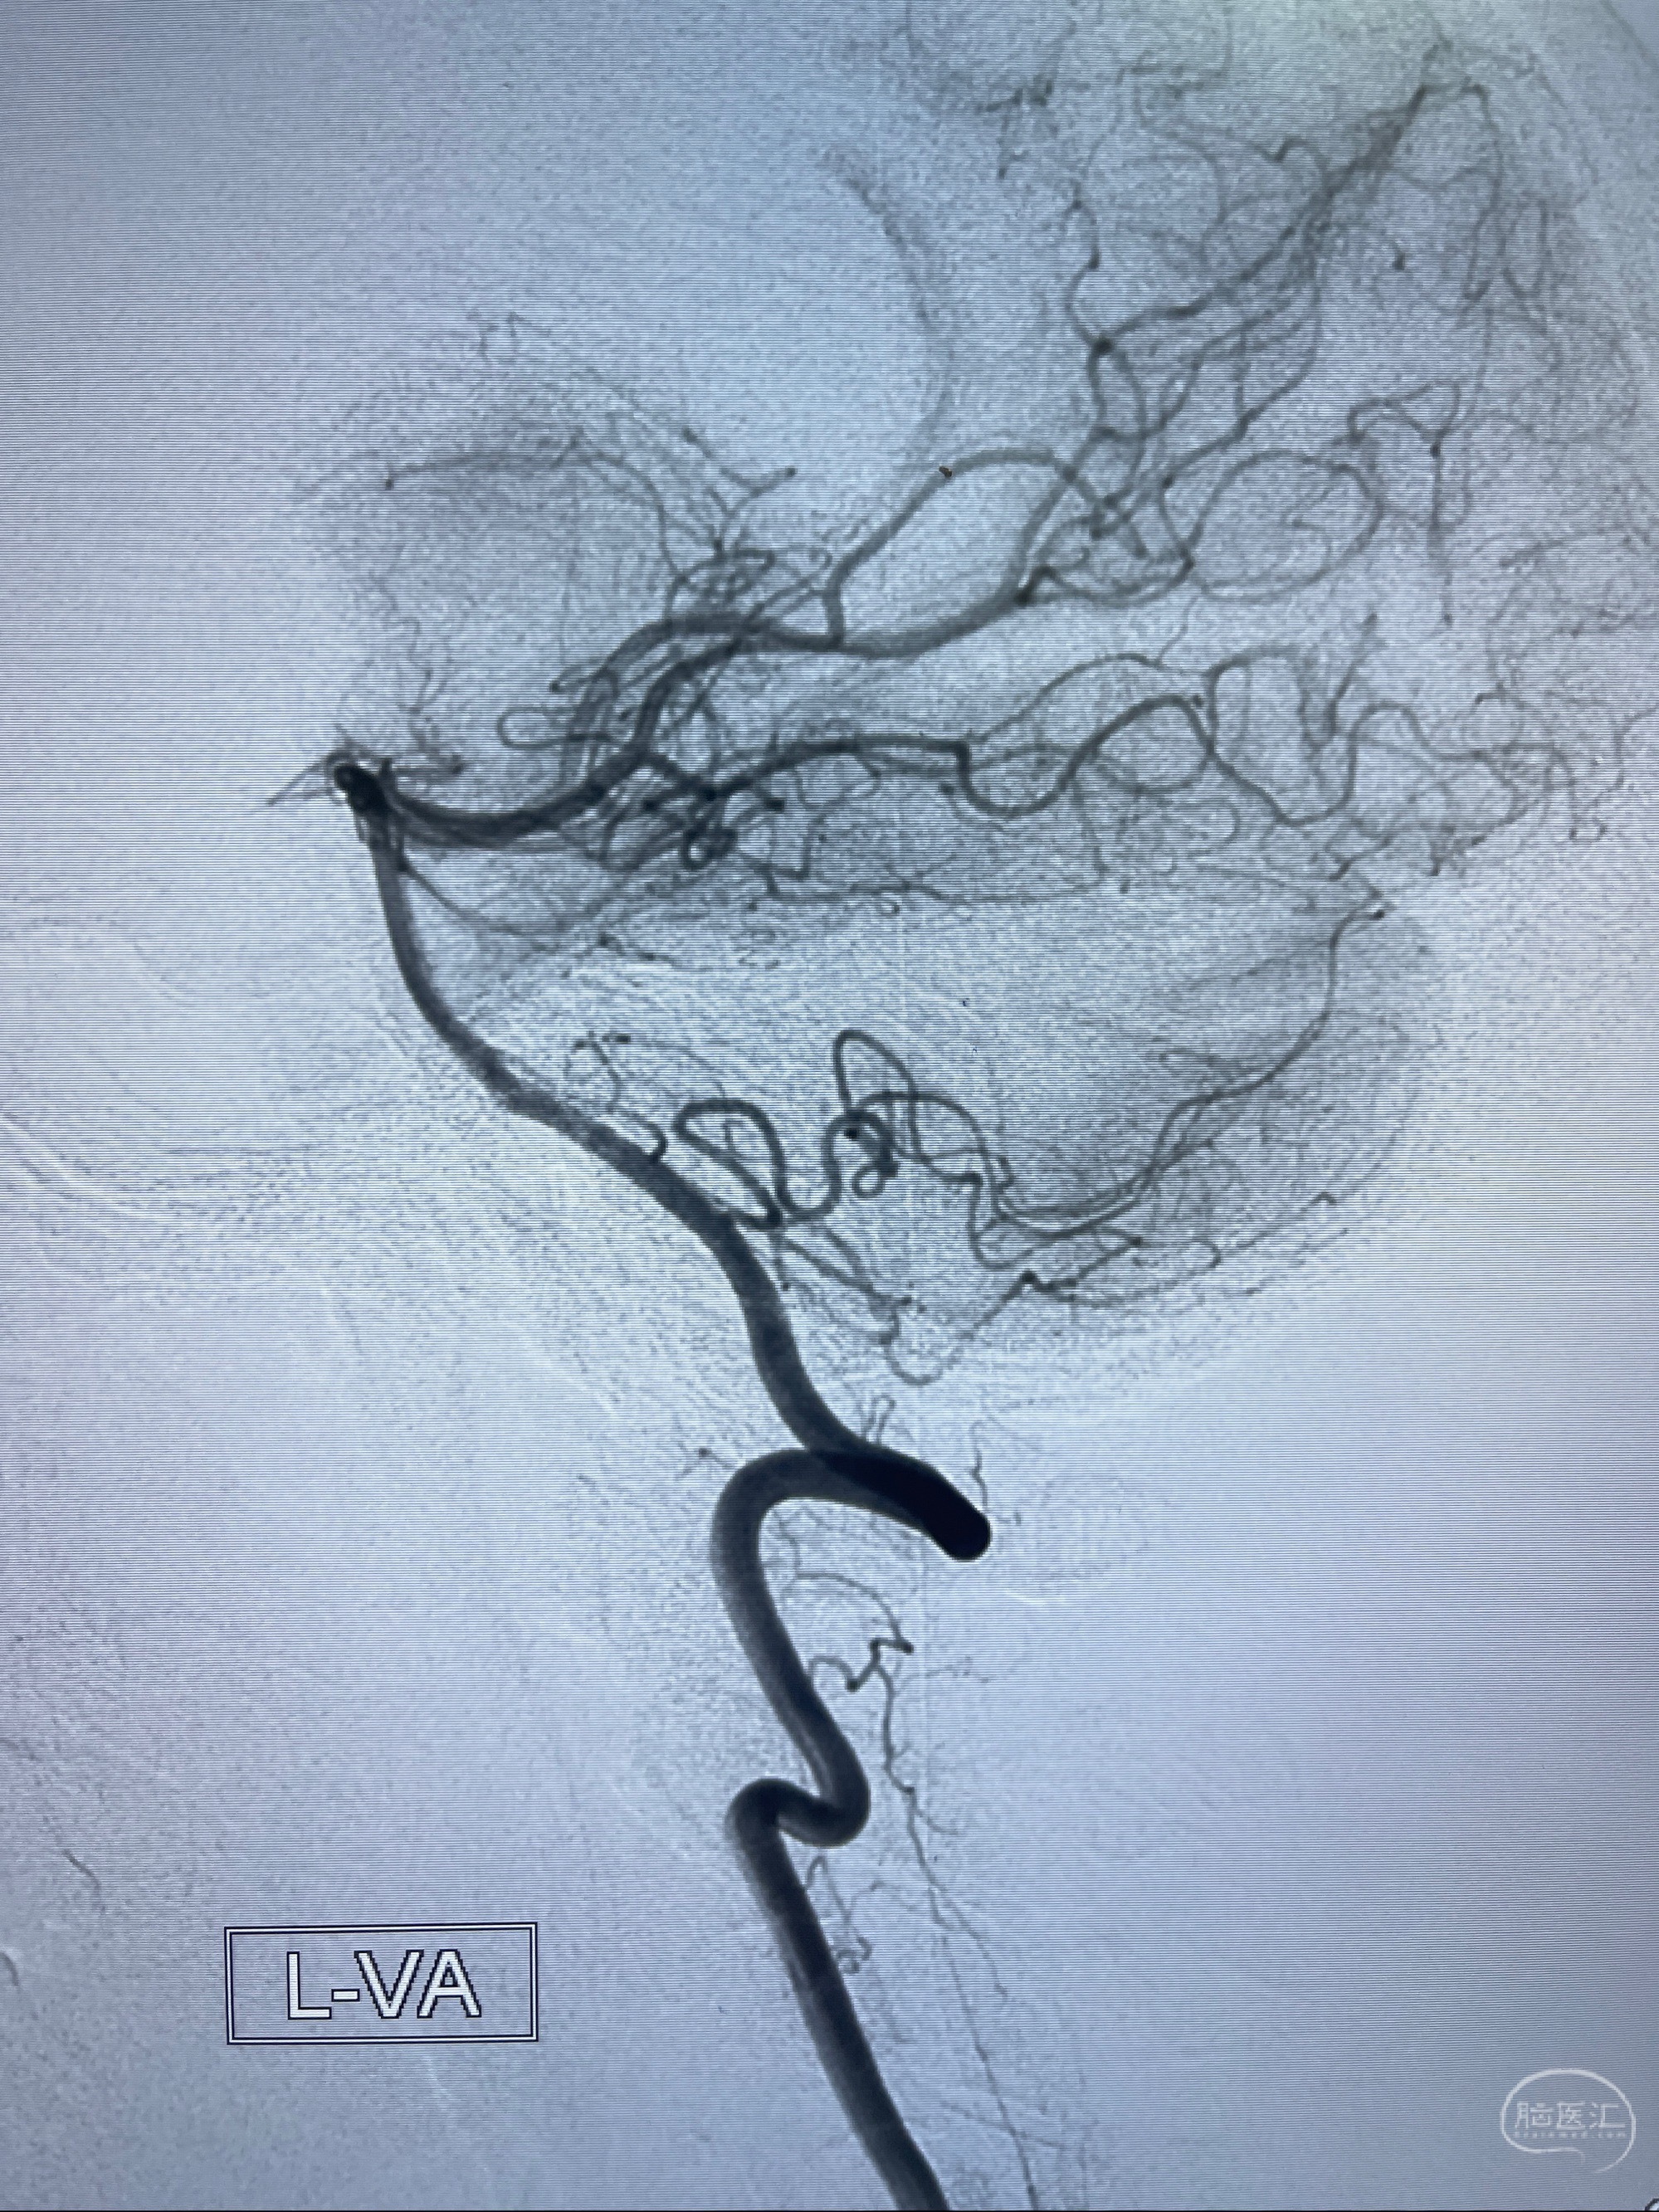

2023-07-27全脑血管造影:双侧颈内动脉眼动脉段动脉瘤,右侧较大

2023-08-01全麻下行双侧颈眼动脉瘤支架辅助栓塞